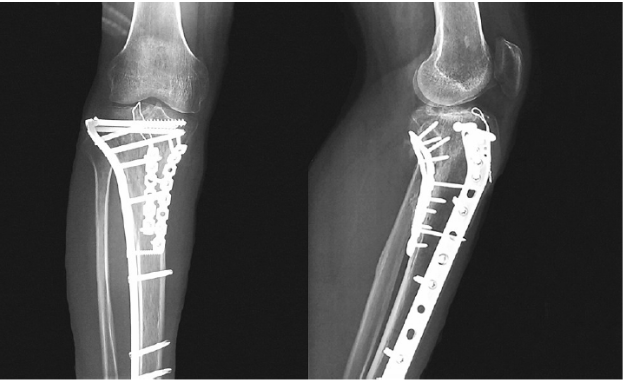

图17 术前X线片

图21 术后X线片

27岁男性患者,在交通意外中受伤。他从自行车上跌落,诉左膝严重疼痛,伤后无法站立。这是个单独的损伤。X线片(图17)和CT(图18~图20)显示左胫骨平台双髁骨折。用两块内固定钢板进行开放复位和内固定(图21)。患者术后1年,影像学表现良好(图22),临床功能(图23)恢复良好。